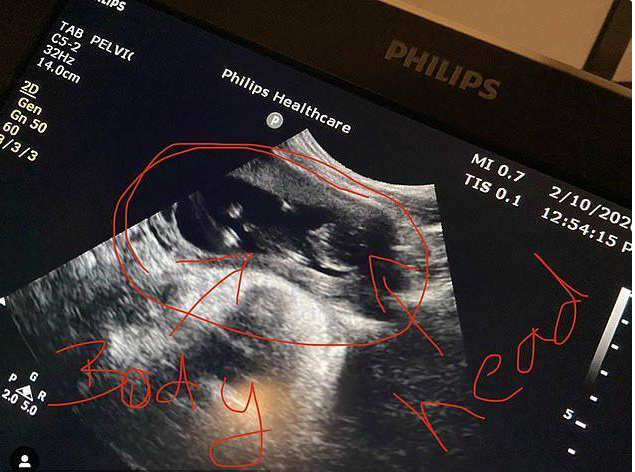

很多人可能会觉得纳闷,为什么他身为一个男性,还能够像女性一样生育呢?其实这是因为凯登之前为了省钱,没有对他的内部和底部的相关构造进行改变,所以具备着女性的生育能力,在生下了第一胎之后,凯登再一次的怀孕了,并且现在也已经第七周了。